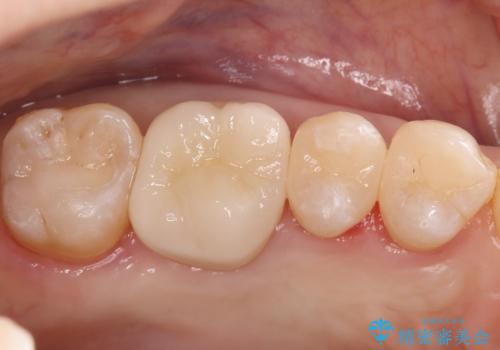

奥歯の銀歯を自然なセラミックに。安心のメタルフリー治療

治療では、まず古い金属のインレーを慎重に取り外しました。金属の下に隠れていた虫歯の再発がないかを確認し、歯を丁寧に形成。その後、精密な型取りから患者様の歯の色に合わせたオーダーメイドのセラミックインレーを作製しました。セラミックは、自然な光の透過性を持つため、周囲の歯と区別がつかないほどの美しい仕上がりとなります。適合性の高いセラミックインレーを装着することで、再発のリスクを抑えつつ、長年のコンプレックスだった銀歯がなくなり、笑顔でも気にならない自然な奥歯を取り戻していただけました。